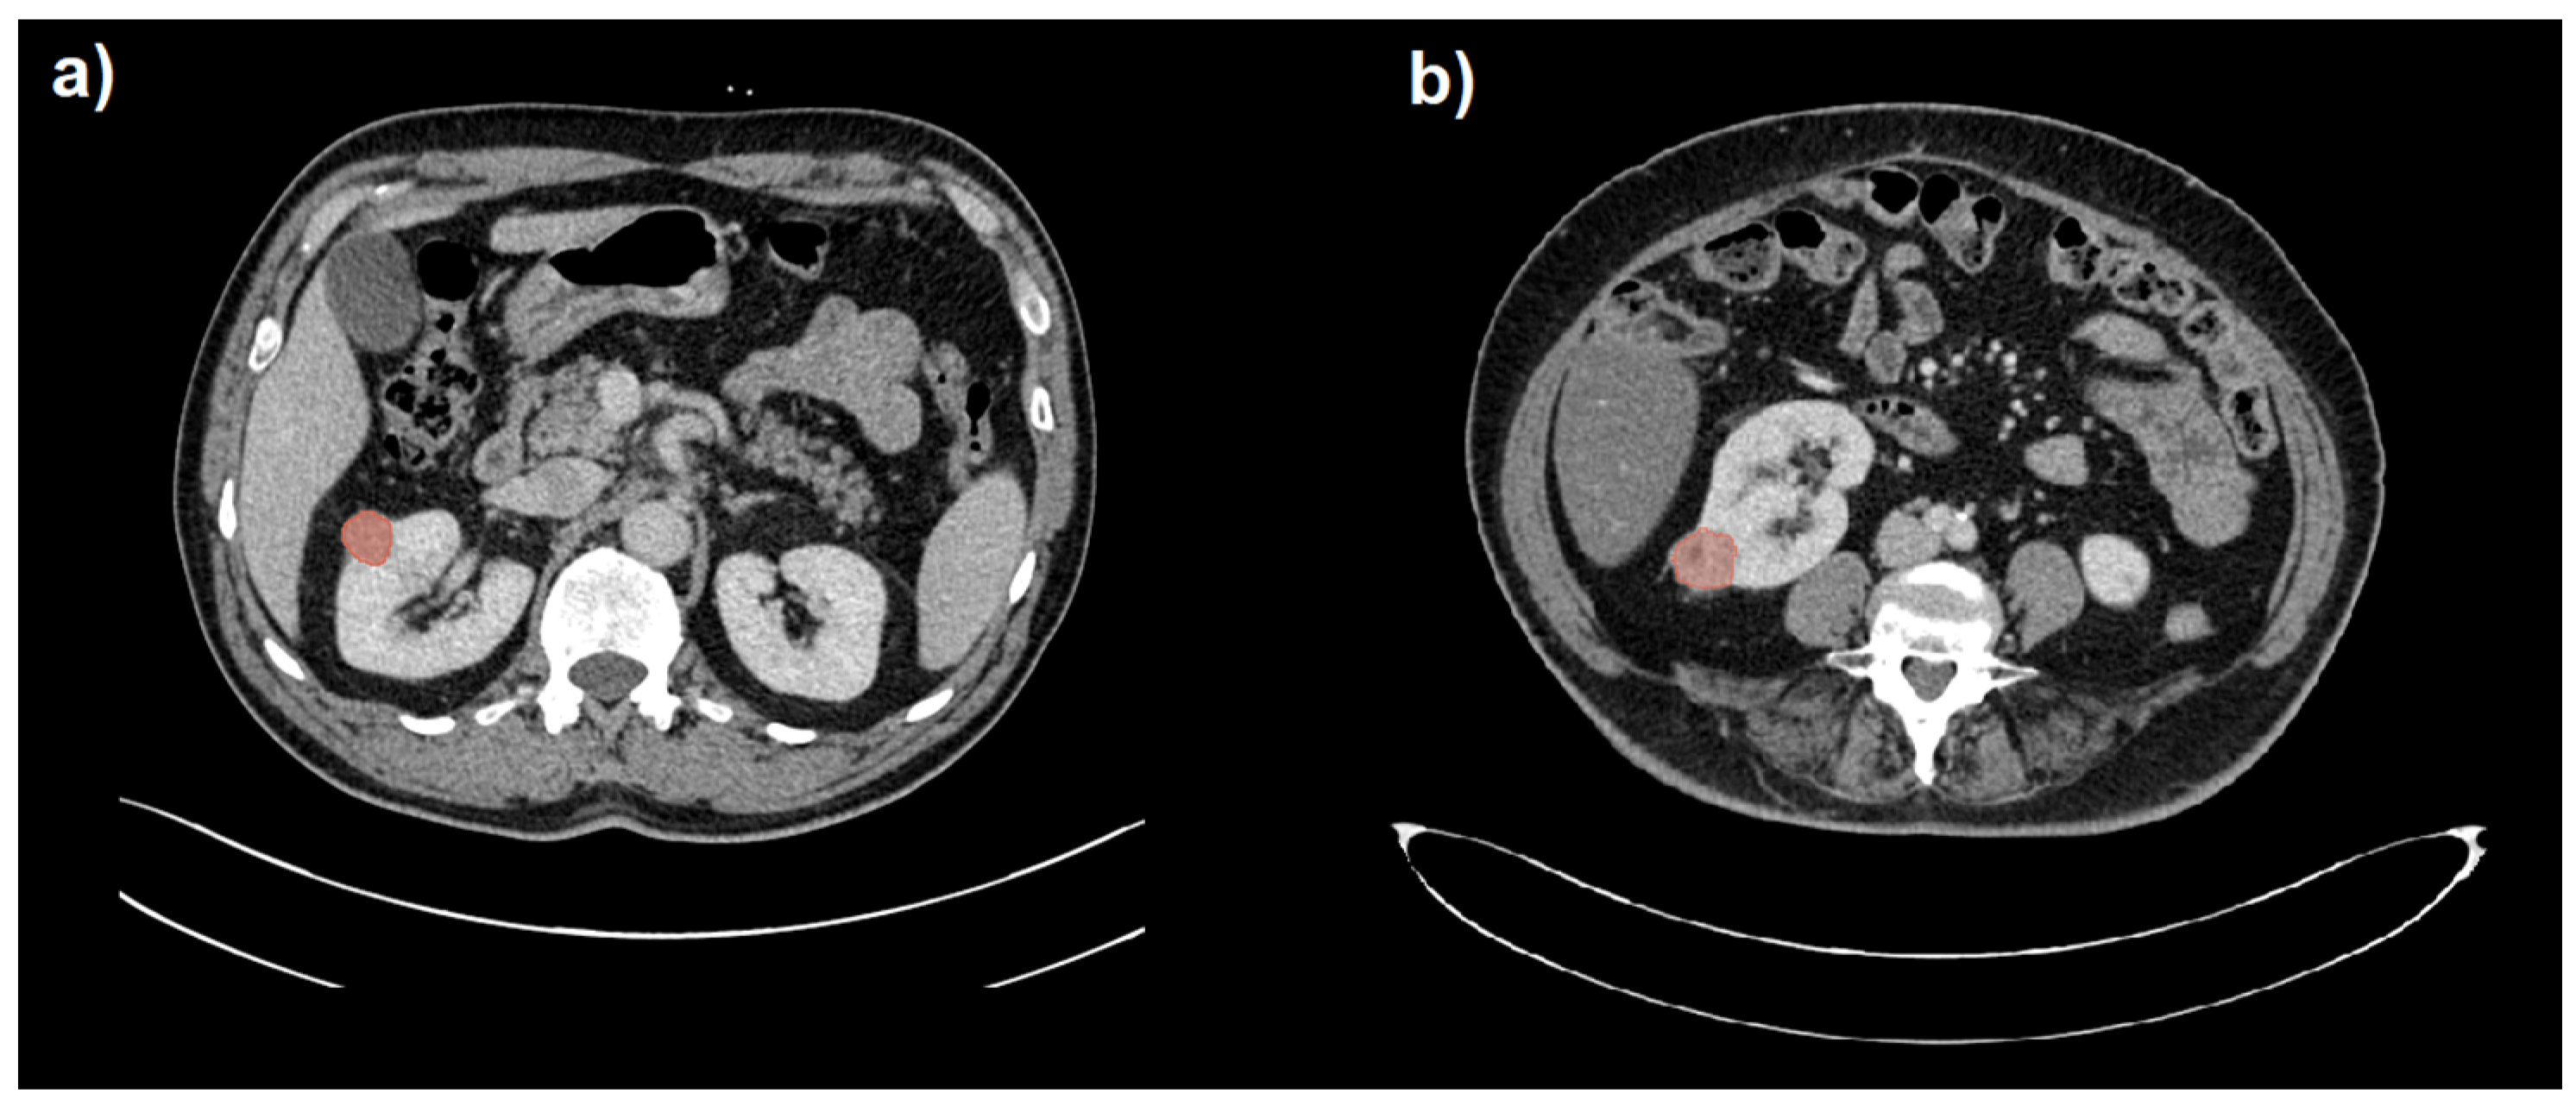

The CT images and related radiological data were extrapolated from the PACS data archiving system of Parma University Hospital. Images were anonymized before their export. Two readers (R1, a radiologist with 15 years of experience in abdominal imaging; R2, a radiologist with 3 years of experience in abdominal imaging) reviewed the CT scans (blinded to clinical and pathological information). The abdominal CTs of the patients included in the study were then imported into 3D Slicer software version 4.10.2 [24]. The radiologist with 3 years of experience (R2) manually delineated the region of interest (ROI) along the edge of the lesion, layer by layer, on the portal venous phase by manually drawing the tumor boundaries. The ROI was used to delineate the boundary of all planes of the renal mass, including necrosis, cystic degeneration and hemorrhage; however, it did not include normal renal tissue or perirenal fat. The volume of interest (VOI) of the lesion was then automatically generated by the software. Finally, another senior radiologist (R1) examined the outlined results on multiplanar reconstruction (MPR) images. Examples of benign and malignant small renal masses with respective segmentations are depicted in Figure 1. No image preprocessing such as wavelet and LoG transformations was performed on CT images before radiomic analysis, so only RFs belonging to the original type were considered. Subsequently, 108 RFs were extracted from the VOI using the SlicerRadiomics® tool [25]. The extracted RFs included both first-order and subsequent-order features, including shape, first-order, Gray-Level-Co-occurrence-Matrix (GLCM), Gray-Level-Run-Length-Matrix (GLRLM), Gray-Level-Size—Zone-Matrix (GLSZM), Neighboring-Gray-Tone-Difference-Matrix (NGTDM) and Gray-Level-Dependence-Matrix (GLDM) functions.

Figure 1. Segmentation (in red) of a benign (a) and a malignant (b) small renal mass (SRM) hardly distinguishable on portal venous phase CT images.